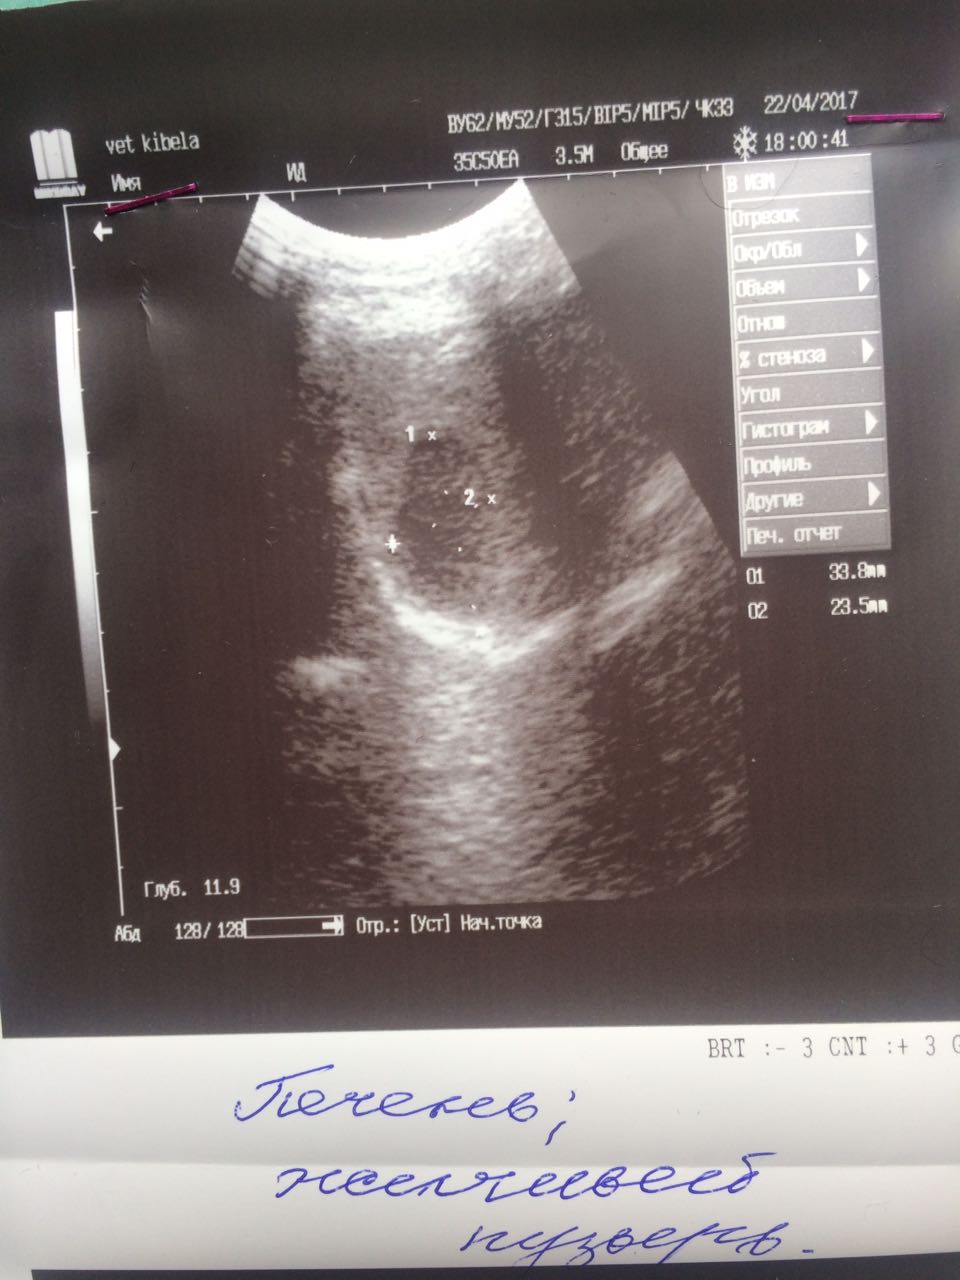

Теперь немного о том что мы нашли на обследование.Не смотря на мои призрачные надежды на доброкачественность образований ,у Лады рак молочной железы. Предположительно похоже на карциному.Конечно хирург сквозь кожу не может разглядеть наверняка ,но полагаясь на опыт может предположить.Из УЗИ мы выяснили ,что пока метастазов в печени,в других органах у нас нет.Есть достаточно большая киста на яичнике и возрастные изменения в почках.